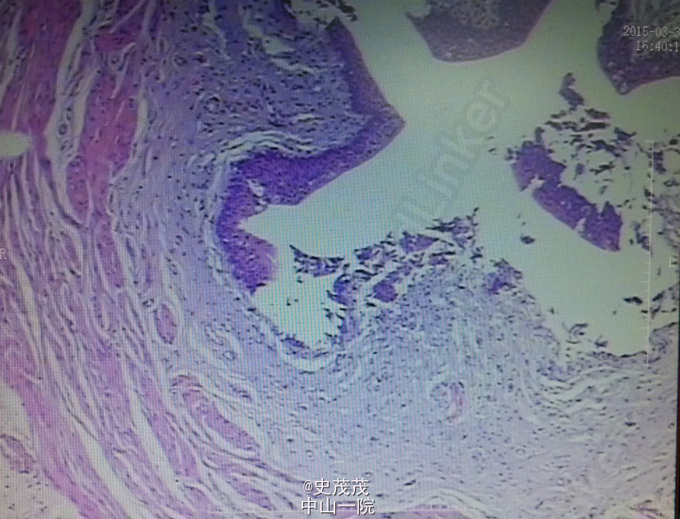

术后病理:右肾及肿瘤:17.5*12*7cm组织一块,切面见肿物14*12cm,大部分坏死,灰白,带输尿管8*0.3cm。镜检肿瘤带厚层纤维组织包膜,与肾实质界限清晰,肿瘤细胞呈小管状分布,细胞立方形,核圆形,大小形态较一致。IHC:CK+、Vim+、CD57+、EMA局灶+、CK7局灶+、CD10-、WT-1(-),Ki67约1%+。病变符合:(右肾)后肾腺瘤,输尿管切端未见肿瘤,肾门周围扪及淋巴结1枚,呈反应性增生,肾门脉管组织未见肿瘤。